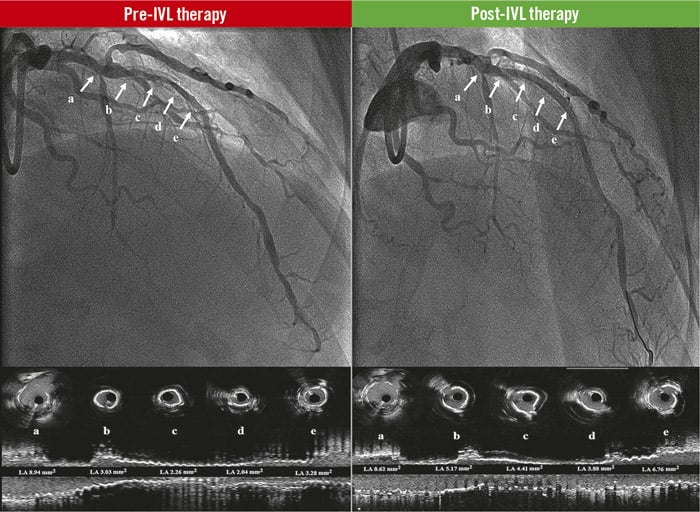

Central illustration. Coronary lithotripsy effect in stent underexpansion. Source: Eurointervention

Pre-IVL therapy: baseline angiogram of the LAD and the corresponding coronary intravascular ultrasound cross-sections (a, b, c, d, e), and longitudinal view of the vessel. The white arrows show significant stent underexpansion with lumen obstruction.

Post-IVL therapy: final result angiograms after coronary lithotripsy therapy of the LAD and the corresponding coronary intravascular ultrasound cross sections (a, b, c, d, e), and longitudinal view of the vessel. The white arrows show significant improvement of stent expansion and lumen obstruction. IVL: intravascular coronary lithotripsy; LAD: left anterior descending coronary artery